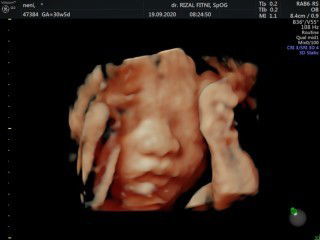

Semoga menjadi pelajaran untuk bunda" semua yg hampir mengalami hal yg sama dg sy. Awal sy telat sy tespek hasilnya positif tp masih buram. Karena ragu sy priksakan di puskesmas. Hpht Menurut sy sendiri tgl 17 maret 2020. Tp memang mens nya hanya sedikit dan dlm waktu 3hr selesai. Sedangkan dr pihak puskesmas mengira bahwa pd 17 maret itu bukan mens tp flek. Jd HPHT sy dr puskesmas masuk di bulan Februari. Dirujuklah sy ke RSU untuk dilakukan kontrol USG. Setelah sy USG hasilnya dikatakan bahwa di usia perkiraan 8w, ternyata sy sudah keguguran. Sontak sy kaget dan gak percaya. Kecewa bgt. Dikasihlah sy obat dan resep. Dokter berpesan kpd saya : Dr : "Bu, ini sy kasih obat dan resep.. nanti obatnya di minum ya bu, perutnya agak mules" sedikit gpp ya?" Sy: "Iya, Dok. (Sambil berfikir "knp perut sy harus mules"? Obat gak bener nih!") Dr : "Minggu depan kontrol ya Bu, klo masih blm bersih terpaksa harus kuret" Sy : hanya menganggukan kepala sj. Dan bergegas plg dg rasa kecewa, sedih, dan gak percaya. Setelah sampai drumah, resep dan obat yg dikasih itu saya browsing kegunaannya untuk apa, ternyata untuk menggugurkan janin. Suami dan keluarga sy tidak meng iya kan apa yg dokter itu bilang. Dg kata lain sy cari second opinion. Akhirnya sy pilih memeriksakan diri di Dokter kandungan saat hamil anak pertama sy. Disana dikatakan janin sy baik" saja. Dan perkiraan dr Dokter ini sm dg perkiraan HPHT sy. Alhamdulillah sampai beberapa kali USG janin sy baik" sj dan semoga sehat selalu. Mohon keikhlasan nya dr bunda" semua,,, supaya janin saya sehat" terus dan dikuatkan sampai dg lahiran nanti🤲🏼🙏🏼. Alhamdulillah sudah masuk 26w. Tp perkembangannya sudah kaya 30w.😊😊😊#bantusharing